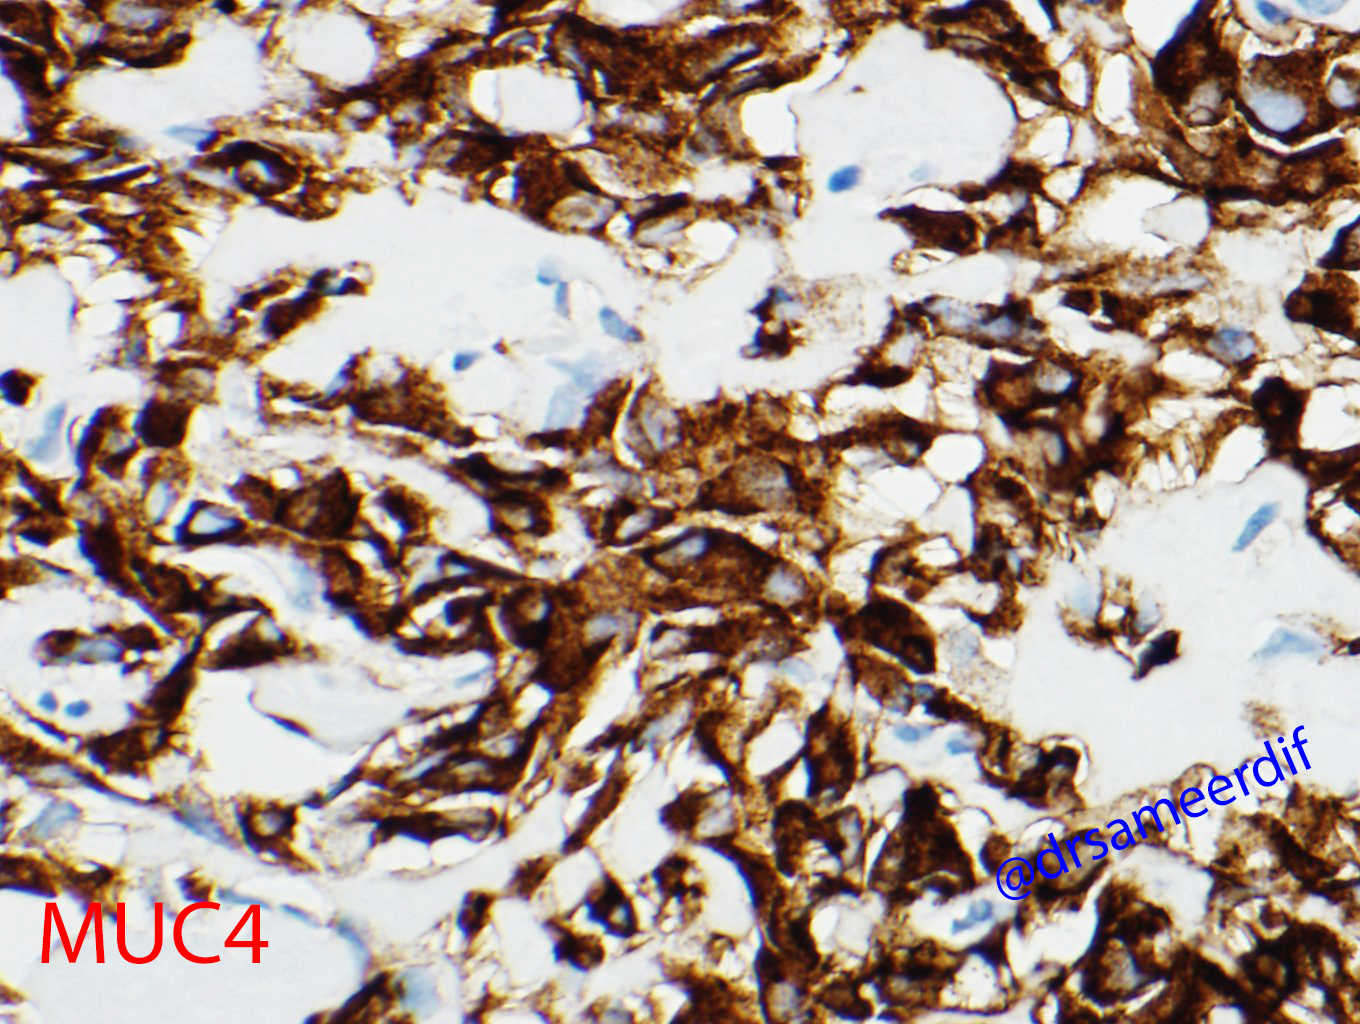

The current biopsy shows a densely hyalinized sclerotic matrix, with focal areas reminiscent of osteoid, lined by small to medium-sized epithelioid cells with clear to eosinophilic cytoplasm and bland nuclei. Mitotic figures are inconspicuous. By immunohistochemistry, the neoplastic cells are positive for MUC4, but negative for CK7, CK20, SATB2, and calcitonin. The morphology and immunohistochemical results are diagnostic of metastatic sclerosing epithelioid fibrosarcoma (SFE) from primary know SFE of the soft tissue.

- MUC4 positive

- EMA IHC positive in about half of the cases.